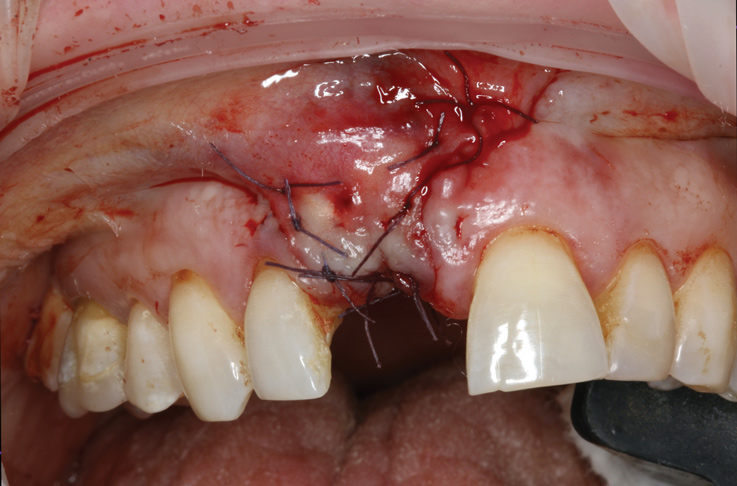

Prior to the initiation of the surgery, the surgical guide was tried in to confirm proper seating and stability (Figure 15). A flapless approach was not considered because the need for further bone grafting at the time of implant placement had been anticipated through the digital planning. A slightly palatal crestal incision was made, followed by two vertical incisions on the mesial and distal aspects of the edentulous site in order to preserve the papilla and avoid additional esthetic compromise to the anterior sextant. Next, a full-thickness flap was elevated to facilitate removal of the tenting screw and permit visualization of the buccal plate (Figure 16). A standard guided protocol was followed to place the implant, and its final position mirrored that of the digital plan. As predicted, the prosthetically driven implant position resulted in an insufficient buccal plate (Figure 17); therefore, additional guided bone regeneration was performed to reinforce the area and prevent future breakdown (Figure 18 and Figure 19). Making periosteal incisions could have compromised the blood supply to the flap, so instead, it was stretched in order to achieve tension free coronal advancement.31The flap was secured utilizing horizontal mattress sutures with additional supportive interrupted sutures to ensure primary closure (Figure 20). An immediate postoperative periapical radiograph (Figure 21) and CBCT scan (Figure 22) were taken, demonstrating a final implant position centered with the planned location of the gingival zenith.

(20.) Tension free primary closure.

Figure 20